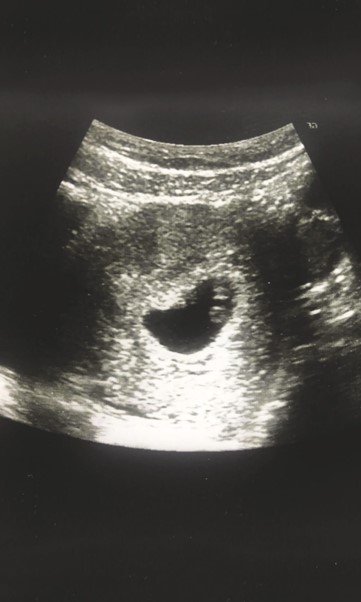

İlk olarak, hücreler bölünmeye başlar ve birçok özdeş yuvarlak hücreye dönüşür. Mikroskopta küçük bir ahududu gibi görünüyorsunuz. Ama yakında hücreler şekil değiştirmeye başlayacak ve giderek daha farklı hale gelecek. Devam edebilirdim, ama kitaptaki her şeyi de vermek istemiyorum.